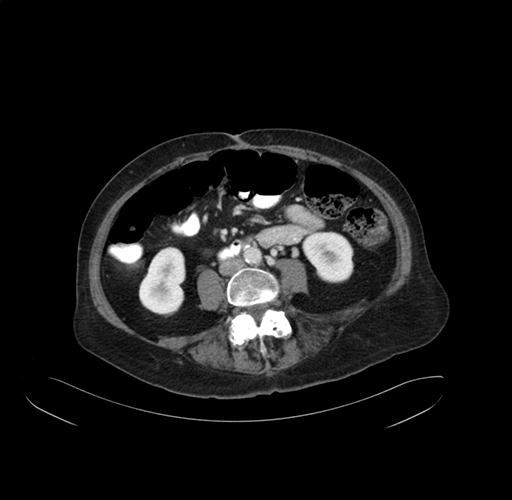

Axial Venous